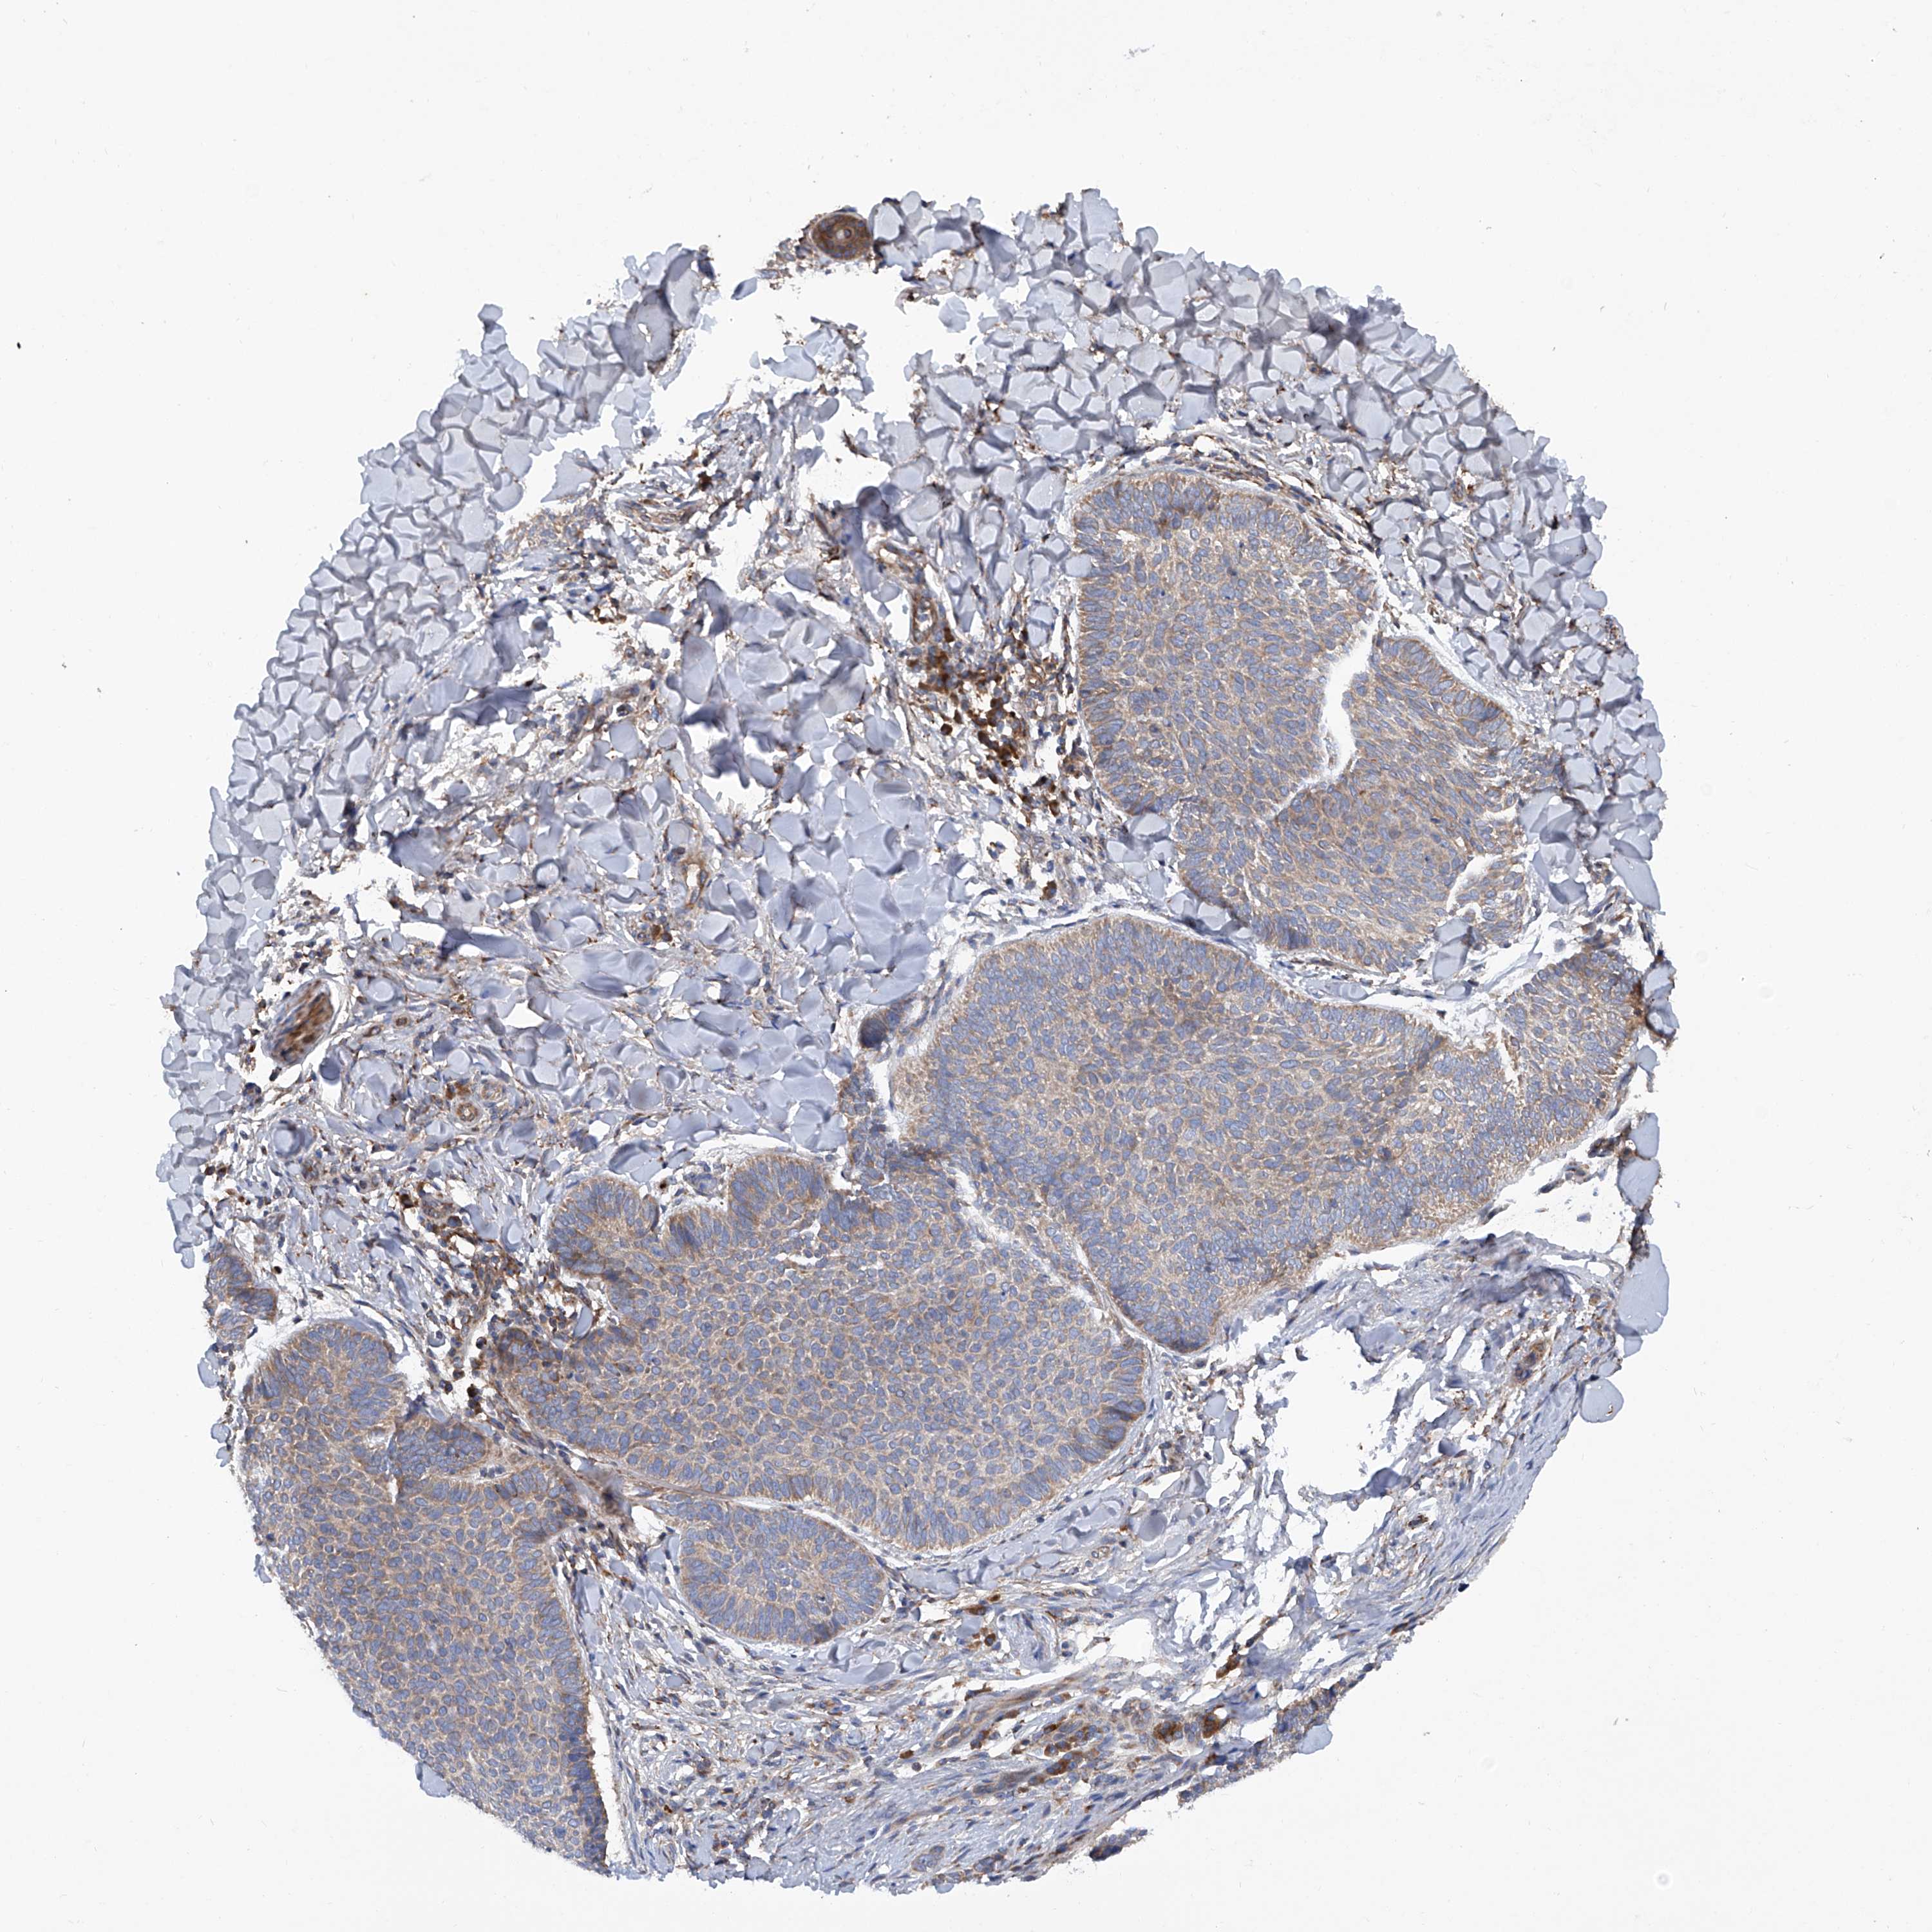

CANCER SKIN CANCER Show tissue menu

Basal cell and squamous cell cancer

SKIN CANCER - Protein expressioni

A mouse-over function shows sample information and annotation data. Click on an image to view it in a full screen mode. Samples can be filtered based on level of antibody staining by selecting one or several of the following categories: high, medium, low and not detected. The assay and annotation is described here.

Each image is clickable and will lead to virtual microscopy that enables deeper exploration of all samples and also displays staining intensity scores, fraction scores and subcellular localization as well as patient and tissue information for each sample.

Antibody HPA031608

Antibody HPA031609

Antibody HPA031610

Basal cell carcinoma

Squamous cell carcinoma, NOS

Squamous cell carcinoma, metastatic, NOS